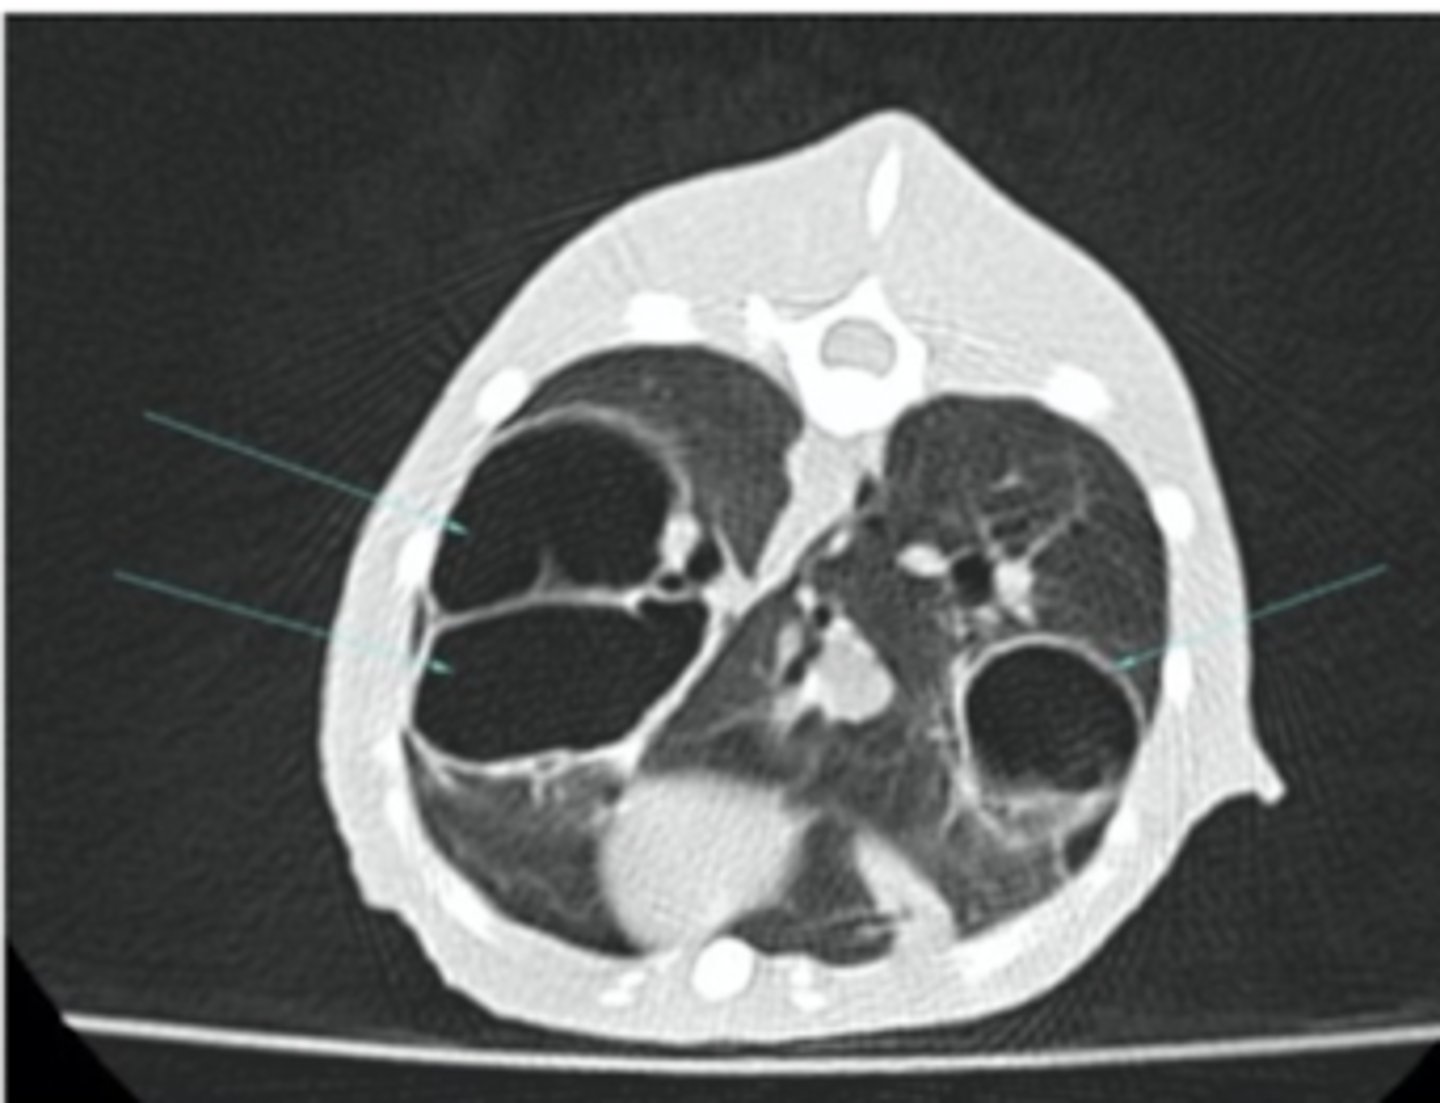

bones and lungs

CT is most useful to visualize what structures?

CT

which is more useful to visualize the lungs- radiographs or CT scans?

computed tomography (CT)

what diagnostic imaging technique was used to create these images?

advantages: creates images without overlapping or reconstructions needed

disadvantages: needs sedation/anesthesia, expensive

what are the advantages and disadvantages of using computed tomography (CT) to produce images?